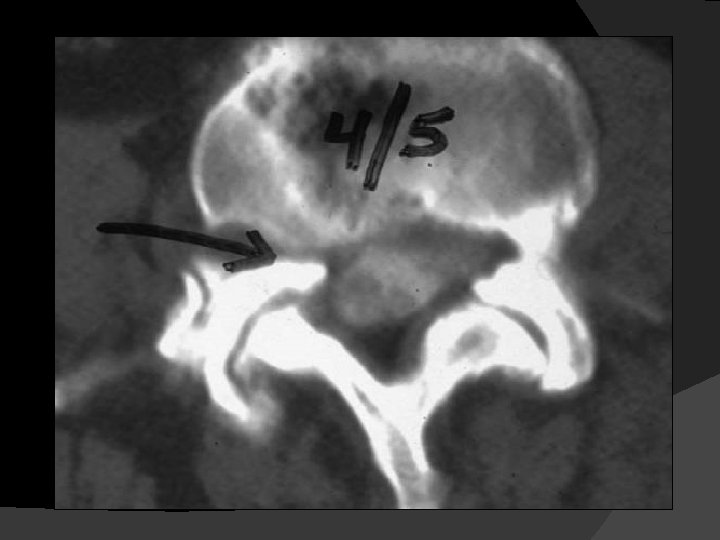

L 3 ASx PSO, T 10 – Pelvis PSF